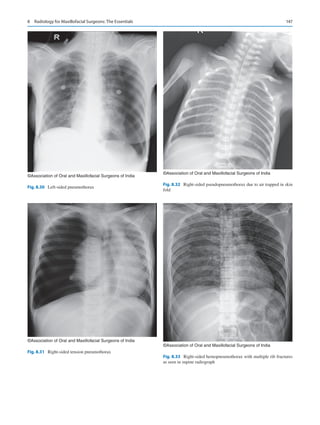

internationally. He emphasized three units of care that oral

and maxillofacial surgeons provide universally—

1.	 Management of maxillofacial trauma.

2.	 Management of oral cancer.

3.	 Management of craniofacial anomalies.